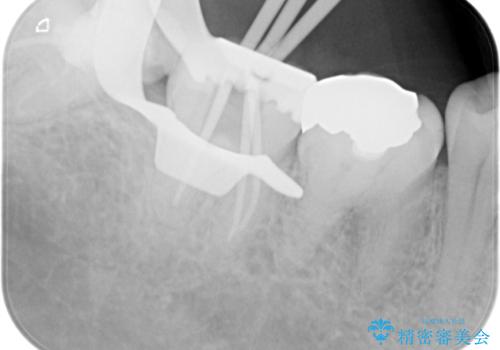

【根管治療】噛んだ時にしみる。最近になってズキズキ痛み、長引く痛みがある

- 噛んだ時にしみる。最近になってズキズキ痛み、長引く痛みがある。とのことで来院されました。

検査結果にて不可逆性歯髄炎の診断を行いました。

顕微鏡にて虫歯を取り除くと、深いクラックラインを認めることができ、クラックラインを全て除去し抜髄処置を行いました。